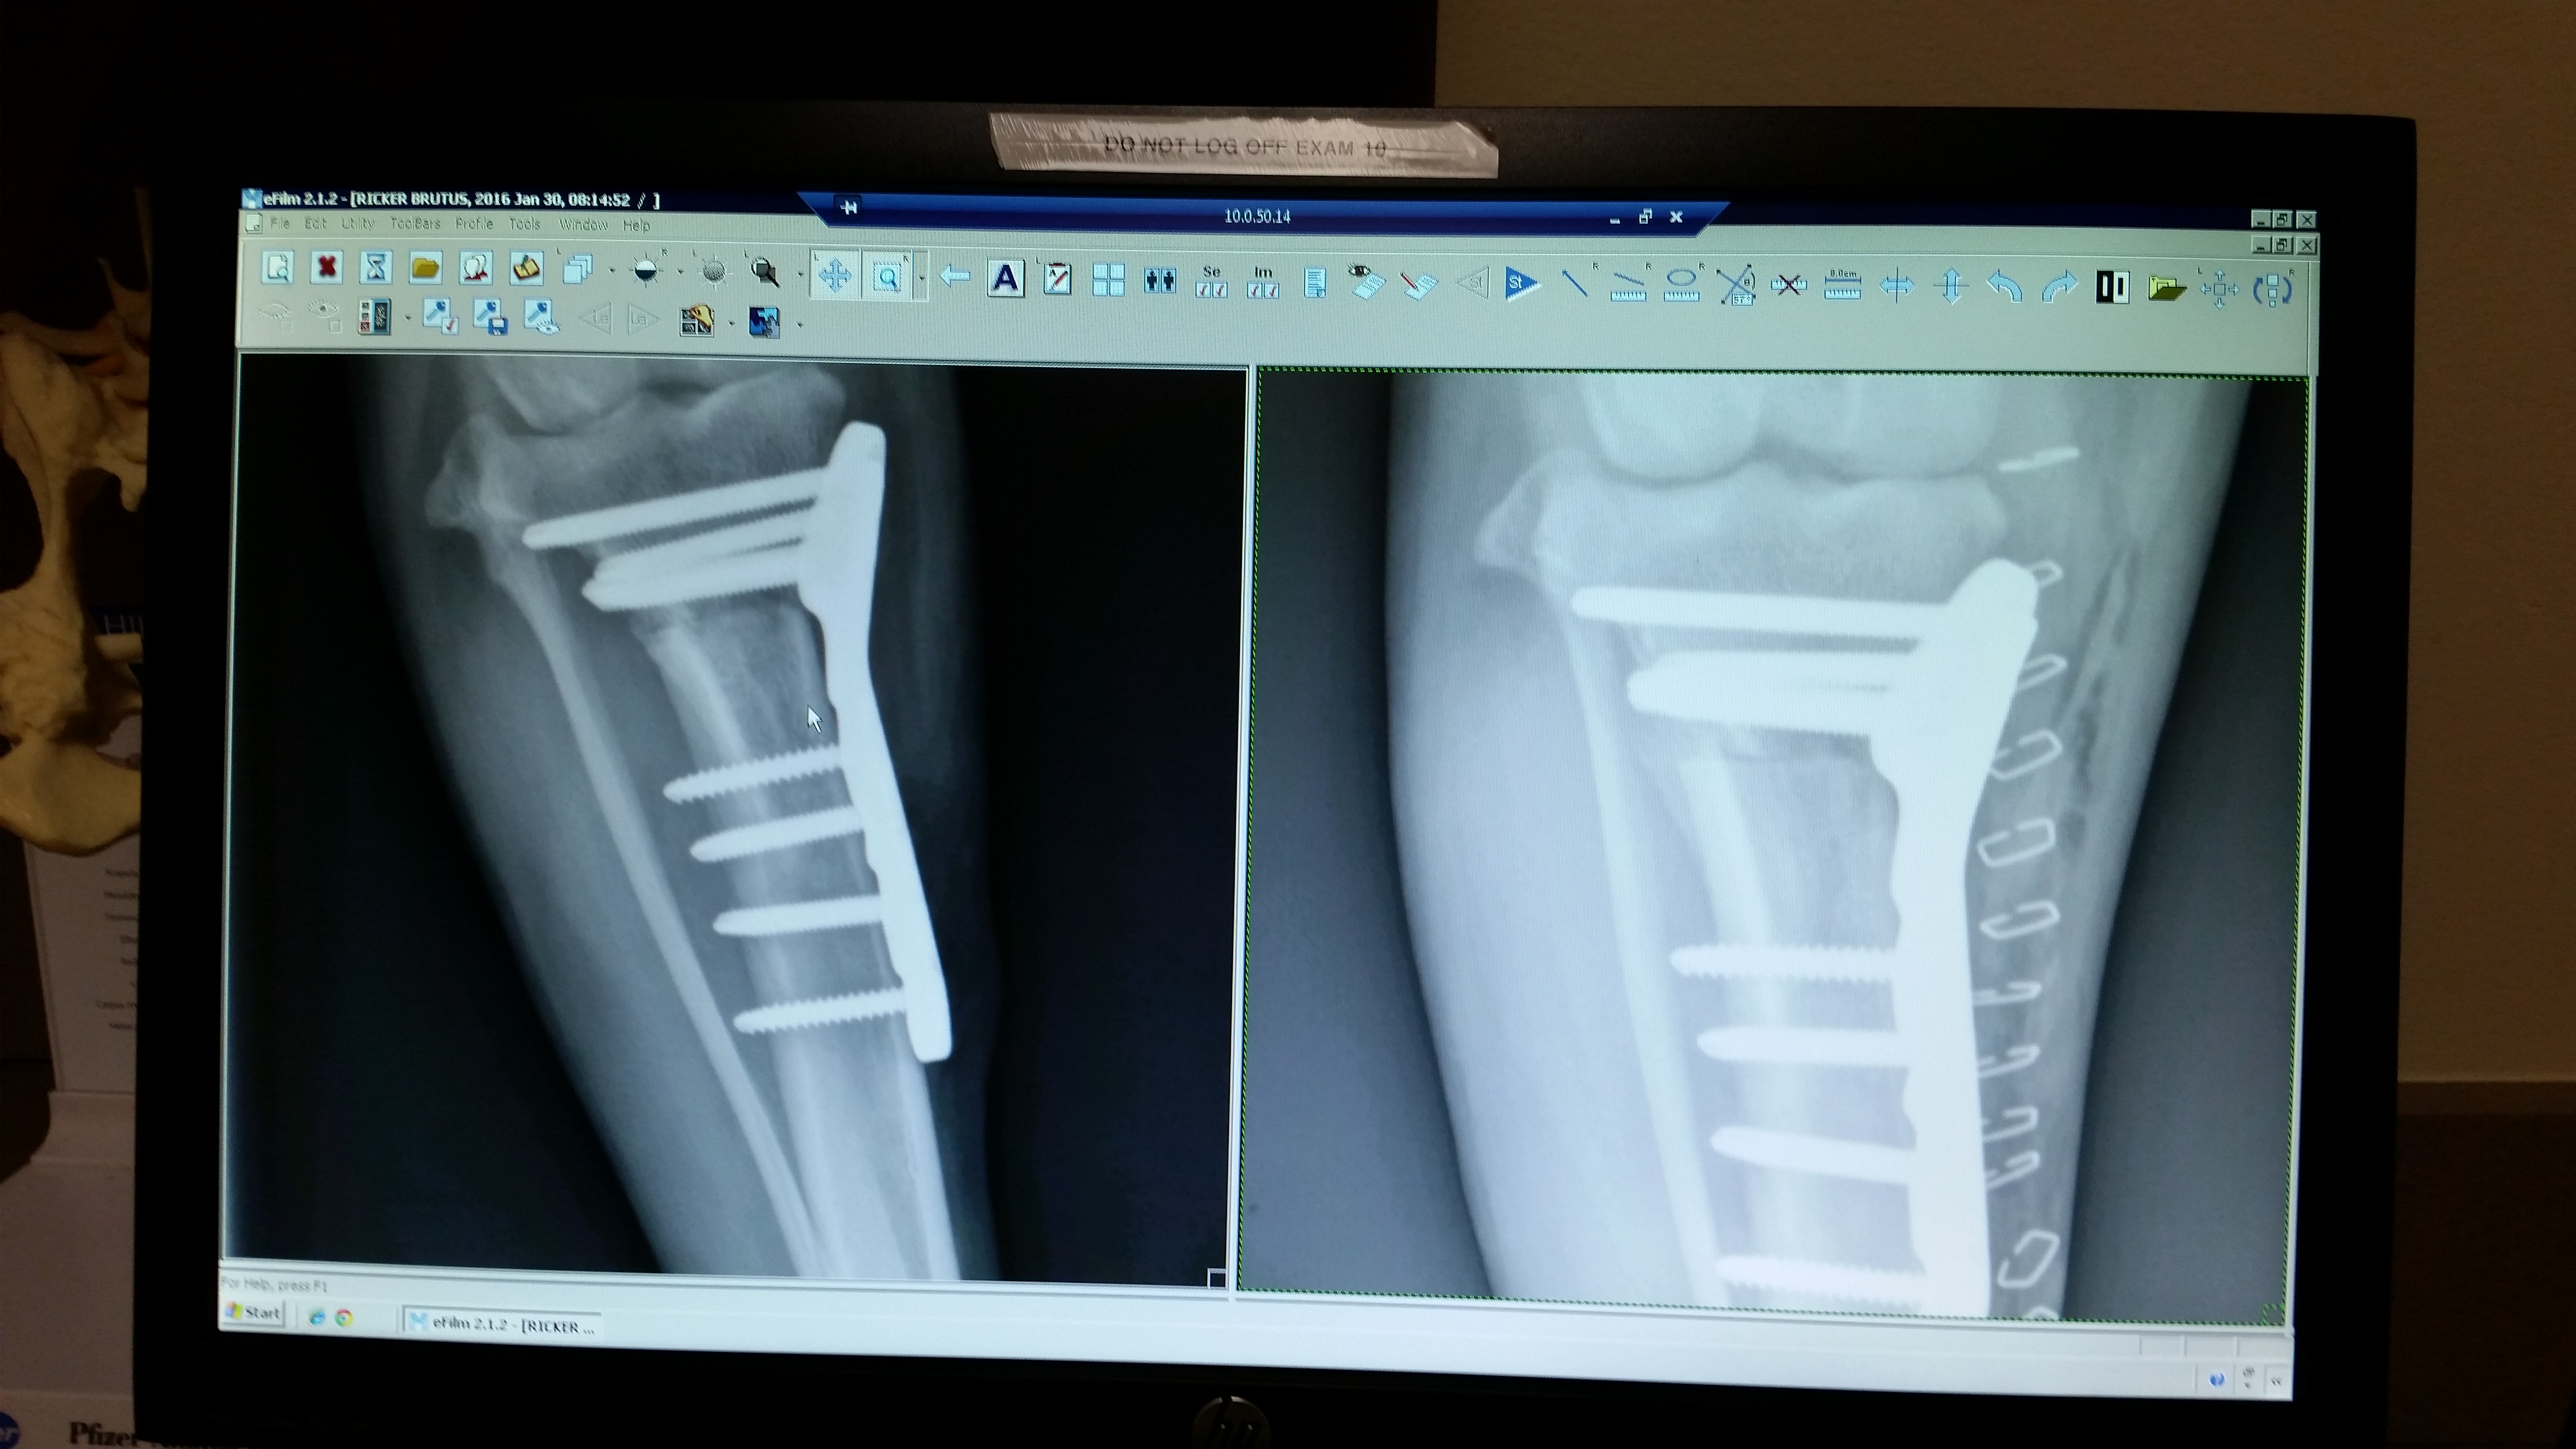

Brutus went in yesterday for his 8-week post-op X-rays and we got great news that his bones are healing nicely. While not 100% healed, we can now spend the next month increasing activity slowly in hopes of a return to normal activity in 4-6 weeks.

Vist our CCL surgery recovery page to track his progress. Unitl then, here are some photos of groggy Brutus from yesterdays procedure as well as his new x-rays.